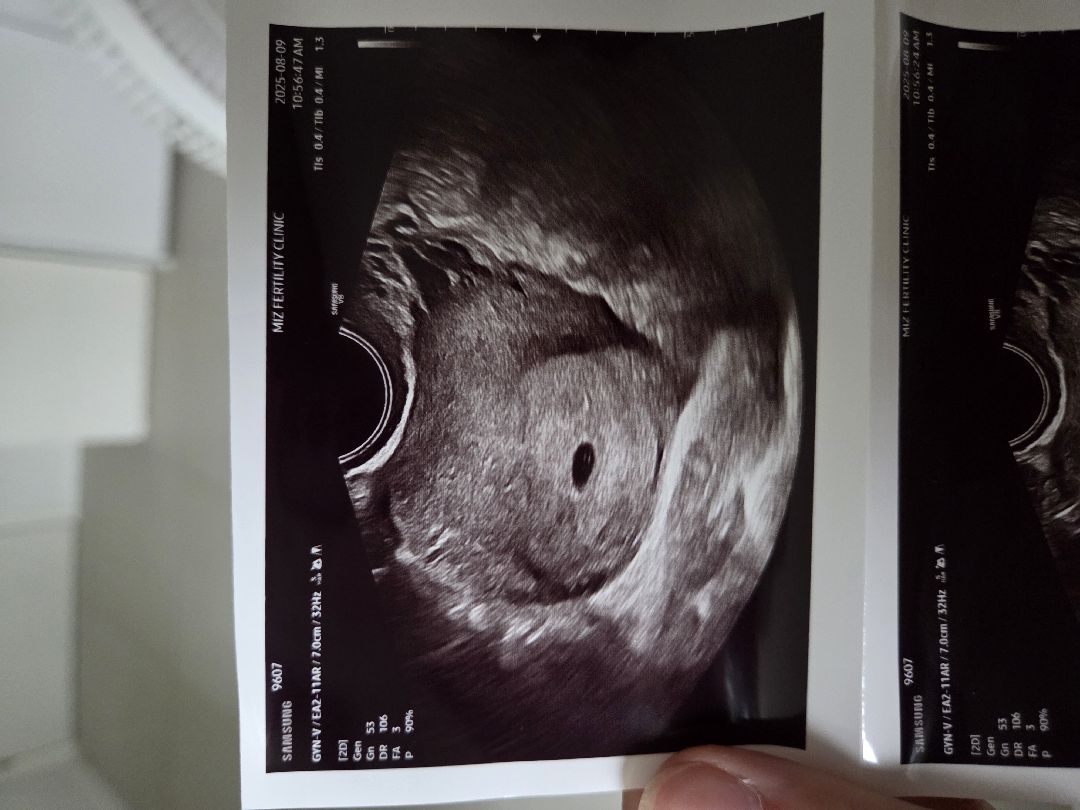

5주차 아기집 질 초음파 사진입니다. 혹시 난황이 보이시는 분 계실까요? 왼쪽에 있는지 오른쪽에 있는지... 질초음파는 좌우반전으로 봐야한다는데 맞나요? 그러면 저는 난황이 왼쪽에 있는걸까요 오른쪽에 있는걸까요?

난황이 보이진 않고, 오른쪽 왼쪽은 좌우반전있는 초음파기계인지 병원에 문의하셔야 할 것 같고요. (혹시 해서 말씀드리는데, 난황이 왼,오로 아기 성별은 정해지지 않습니다^^ 태몽이나 입덧만큼이나 신빙성이 없더군요ㅎㅎ)

이 사진엔 난황 안 보여요 근데 5주차엔 일반적으로 아기집만 보여요 일찍 보이는 분들도 있긴 하겠지만 6주 정도에 난황 보일 거예요

아기집밖에 안보이는데요..?